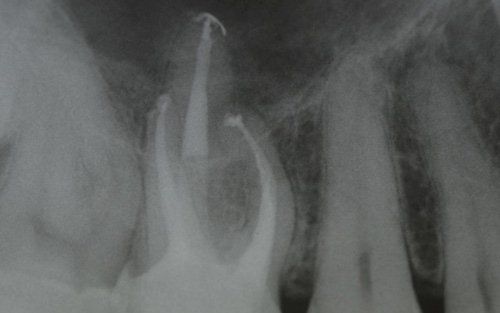

This treatment should be reserved for teeth that have irreversible pulp pathology (the nerve of the tooth) or an infection of the dental canals that has caused an abscess (acute apical periodontitis) or a granuloma (chronic apical periodontitis). While in the first two cases the tooth is very painful and the patient immediately seeks the dentist, the case of the chronic form is often silent, and therefore the patient may not notice anything for a medium to long period of time. In such conditions, it is only an X-ray image, taken during routine check-ups, that detects its presence. Root canal therapy can be completed by placing a latest-generation post inside the canal, as a means of retaining the material used for the reconstruction of the tooth. It will be up to the clinician to decide whether or not the restoration requires this additional anchoring system.